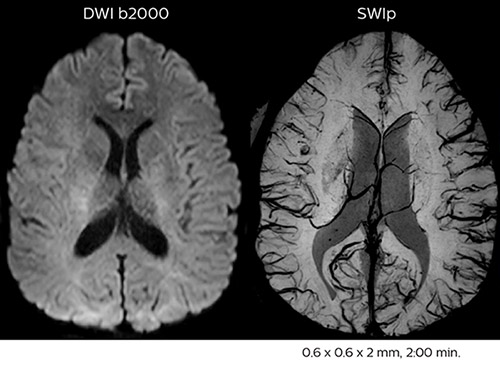

Using MultiBand SENSE allowed the staff to improve their diffusion quality. “Our diffusion sequence was already fast before, about 40 seconds. Now with Elition, it still lasts 40 seconds, but we improved the spatial resolution by 0.2 mm and use high b-values to be more sensitive to visualize changes related to acute stroke,” says Dr. Savatovsky. “We now also developed a high resolution DTI sequence (1.3 x 1.3 x 2 mm) that can be reformatted and takes 2 to 5 minutes depending on the coverage. We use it every time we have a doubt, or when we expect the diffusion to be abnormal but don’t see that on the fast sequence. We occasionally spot small ischemic infarctions that would not have been visible with the regular diffusion sequence.”

This is an example of acute ischemic stroke with distal occlusion of the right posterior cerebral artery. Note the improved visibility of the ischemic territory on the diffusion weighted image with high b-value. The 3D FLAIR shows a distal PCA occlusion. The fast SWIp depicts the thrombus on the isolated second echo image. The total scan time (including SmartBrain, preparations and a fast 3D T1w TSE Gd) is 8:00 minutes.